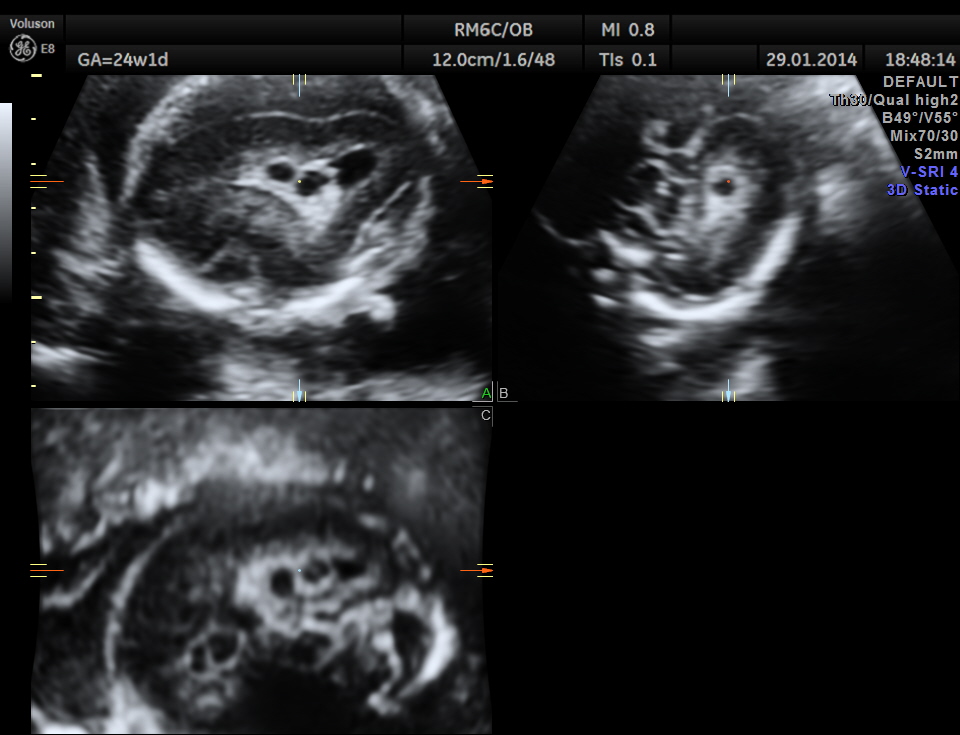

The following images were obtained. Unilateral choroid plexus cyst was seen .

Images of the other organs are given below.